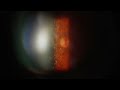

Color-Accurate, True-to-Life Results